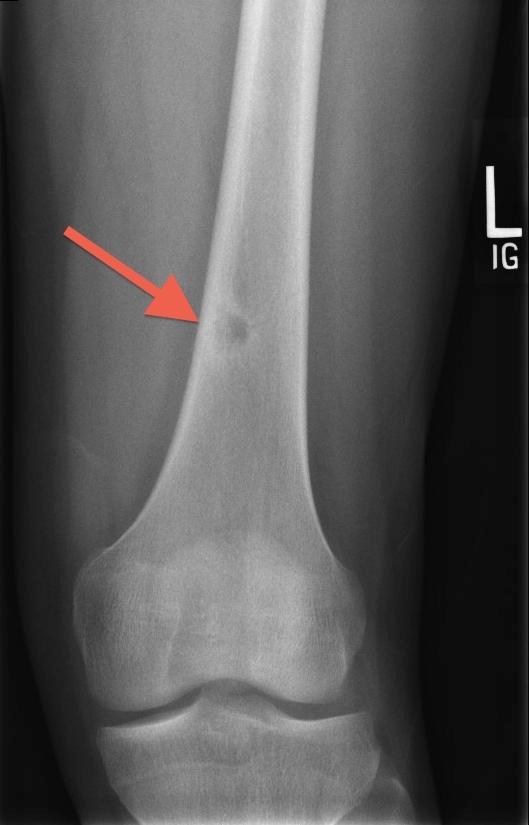

Osteoid Osteoma

Osteoid osteoma is a benign, bone-forming tumor that typically occurs in adolescent boys. The femur (particularly the proximal bone), tibia, and spine are the most common sites affected. Patients develop increasing pain that is worse at night and is unrelated to physical activity. Pain relieved by nonsteroidal anti-inflammatory drugs (NSAIDs) is a classic feature that is strongly suggestive of the diagnosis; the absence of this finding should raise suspicion for alternate diagnoses.

Tenderness, deformity, or swelling may be present on examination; however, adolescents may have no focal examination findings. X-ray shows a characteristic small, round lucency with sclerotic margins and sometimes central ossification. NSAIDs are prescribed for symptomatic relief, and serial imaging is performed to monitor the lesion. Surgical resection is typically reserved for patients with refractory symptoms, as most lesions resolve spontaneously over several years.